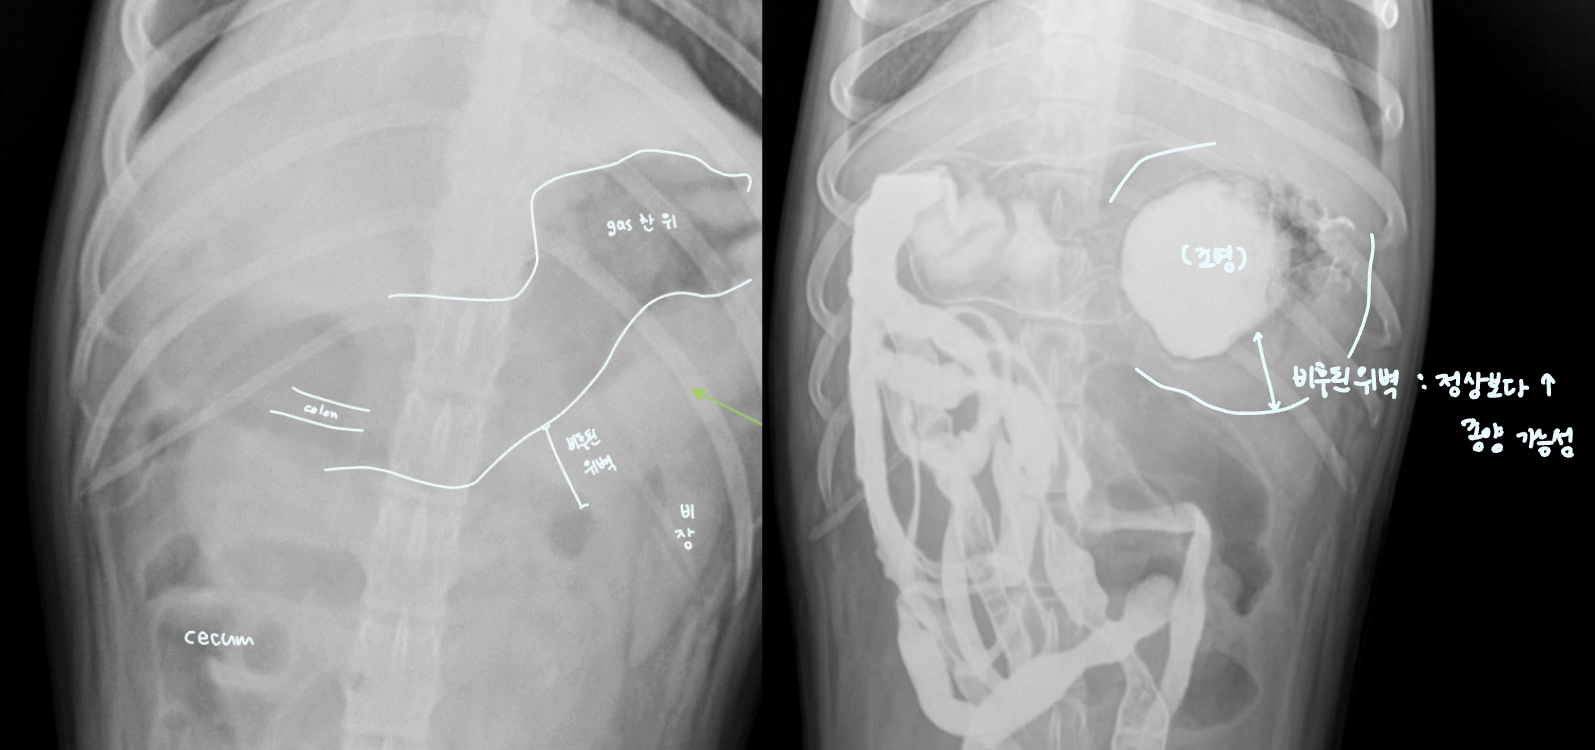

์ํ์ฅ : GD vs. GDV

- ๊ฐ๋ณ์ key point๋ pylorus์ ์์น & ์์ ๋ถํํ(compartmentalization) !

- ์ ์์ ์ธ ์์น๋ ์ธ์ธก์์์ ์๋์ชฝ, ๋ณต๋ฐฐ์์์ ์ผ์ชฝ์ ์์น.

- GD๋ ์๊ฐ ํ์ฅ๋์ด ์์ผ๋, ์์น๋ ๊ทธ๋๋ก.

- GDV๋ ์ฅ์ด ๊ผฌ์ด๋ฉด์ ์์น๊ฐ ๋ฌ๋ผ์ง๋ฏ๋ก, pylorus์ ์์น๊ฐ ์ธ์ธก์์์ ์์ชฝ

| GD | GDV | |

|---|---|---|

| VD | - greater curvature ์ผ์ชฝ(์ ์) * 360๋ ํ์ ์์๋ ์ผ์ชฝ์ ์์น | - greater curvature ์ค๋ฅธ์ชฝ (180๋ ์ผ์ ) - duodenum ์์น๋ ํจ๊ป ๊ผฌ์ |

| RL | - pylorus๊ฐ ์๋์ชฝ(์ ์) | - pylorus ์์ชฝ - ์์ ๋ถํํ(compartmentalization) : ๋ถ๋ฐฉ ํ์ธ - gastric band (soft tissue) ๊ด์ฐฐ |